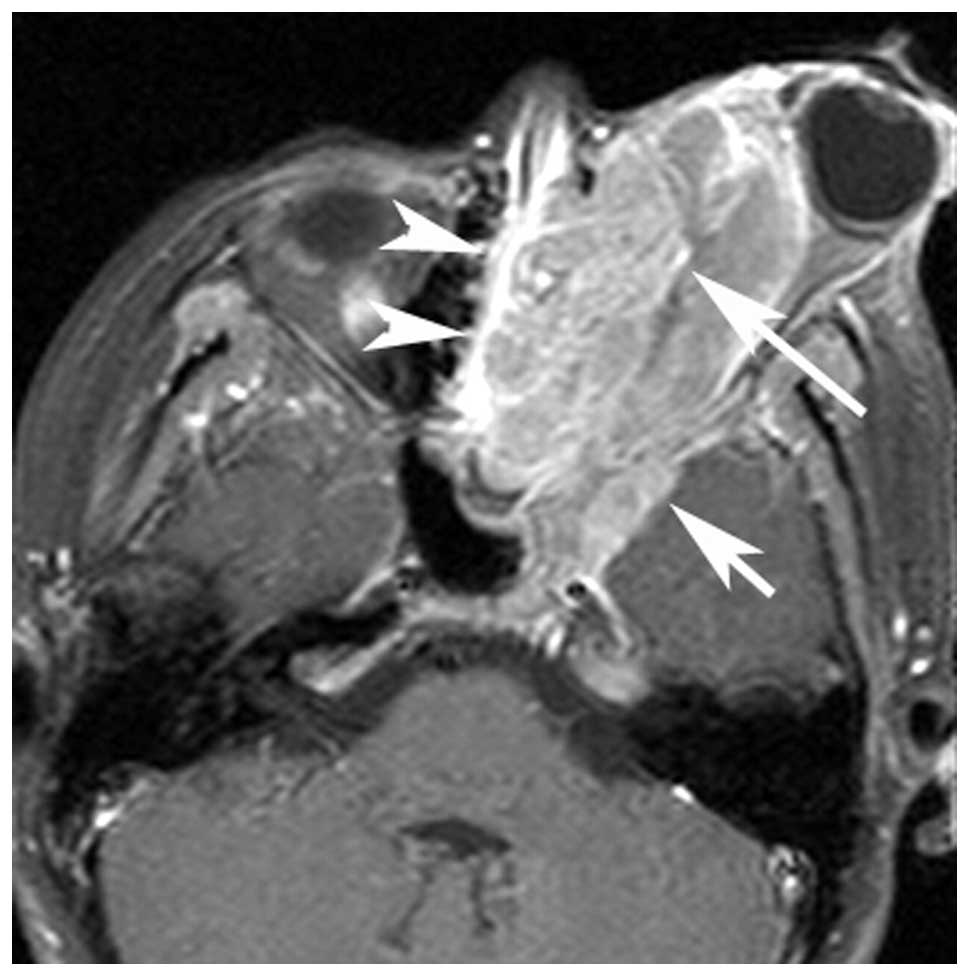

Computed Tomography And Magnetic Resonance Imaging Observations Of

www.spandidos-publications.com

www.spandidos-publications.com

rhabdomyosarcoma neck head embryonal axial tomography computed imaging magnetic observations resonance ol figure